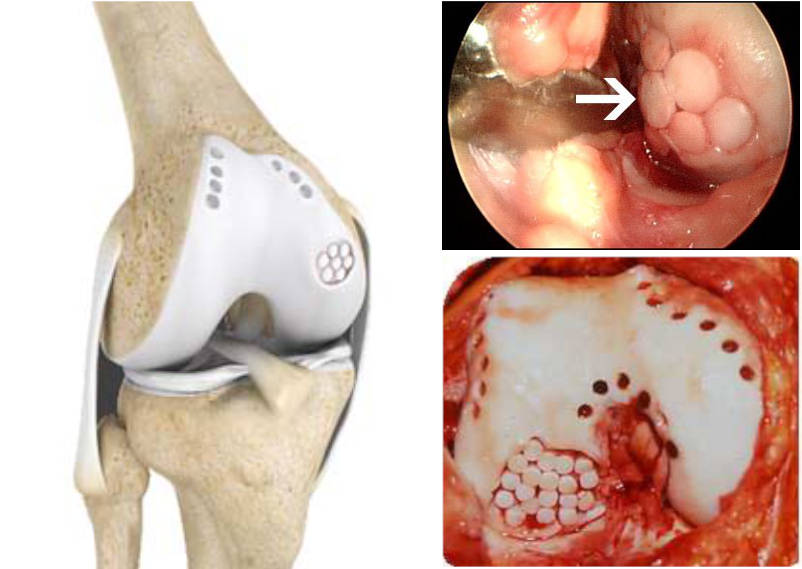

Τεχνική των μικροκαταγμάτων όπου με ειδικό εργαλείο δημιουργούνται μικρές οπές στο σημείο της βλάβης στο υποχόνδριο, ώστε να απελευθερώνεται αίμα πλούσιο σε αναγεννητικούς παράγοντες στο σημείο της βλάβης με αποτέλεσμα προοδευτικά να σχηματίζεται χόνδρος ινώδης στην περιοχή. Ο συγκεκριμένος χόνδρος δεν έχει τις ιδιότητες του υαλοειδούς χόνδρου είναι λιγότερο εύκαμπτος και ελαστικός. Η τεχνική δείνει να είναι αρκετά αποτελεσματική σε βλάβες χόνδρου μέχρι 2 εκατοστά και καλή ποιότητα υποχόνδριου ιστού.

Τεχνική μεταμόσχευσης αυτόλογων οστεοχόνδρινων κυλίνδρων για βλάβες μέχρι 4 εκατοστά (OATS-mosaicplastic), λαμβάνονται κυλινδρικά οστεοχόνδρινα τμήματα από μη φορτιζόμενες περιοχές της άρθρωσης και τοποθετούνται στη βλάβη με αποτέλεσμα να έχουμε υαλοειδή χόνδρο.

Τον τελευταίο χρόνο, η ομάδα της Β' Ορθοπαιδικής Κλινικής του Ιασώ Θεσσαλίας χρησιμοποιεί την τεχνική Graftnet με εντυπωσιακά αποτελέσματα, όπου στον ίδιο χρόνο συλλέγει υγιή χόνδρο από μη φορτιζόμενη επιφάνεια, τον δυναμοποιεί και ενεργοποιεί ανακατεύοντας τον με αυτόλογους αυξητικούς παράγοντες και τον επανατοποθετεί στη περιοχή της βλάβης όπου θα αναπτυχθεί νέος αρθρικός χόνδρος.